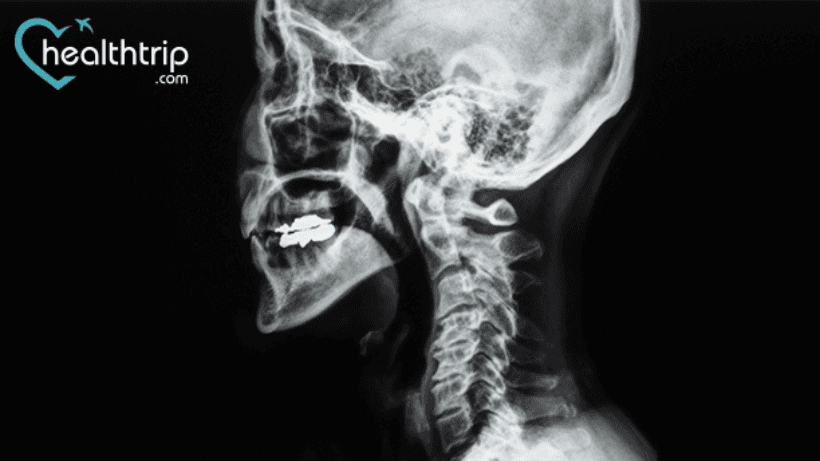

На шее выполняется операция передней шейной дискэктомии и спондилодеза (ACDF) для удаления поврежденных дисков или костных шпор.. И если вам интересно, сколько лет сохраняется результат таких операций, то вы на правильной странице. Здесь мы кратко обсудили его показатель успеха и другие факты, которые вам нужно знать после того, как он был Медицинское лечение.

Сколько лет сохраняется результат операции ACDF?

ACDF улучшает результаты лечения всех первичных диагнозов и, как было доказано, сохраняется более десяти лет.. Вторичные операции были выполнены для восстановления псевдартроза и для лечения симптоматической дегенерации прилегающего уровня.